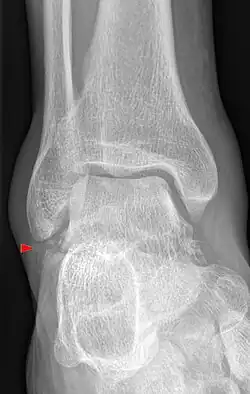

Snowboarder’s Ankle bezeichnet einen früher selten diagnostizierten, speziellen Knochenbruch des Sprungbeins, der mit der Verbreitung des Snowboards im Wintersport deutlich an Häufigkeit zugenommen hat.[1] Betroffen ist der Processus lateralis tali, ein Fortsatz des Sprungbeins, der nach außen weist und einen Teil der Gelenkverbindung mit dem Außenknöchel des Wadenbeins und nach unten zum Fersenbein bildet.

Die Verletzung stellt sich mit Schmerzen und Schwellung in der Fußwurzel und außen am Fuß dar. Diese Befunde können leicht mit einer Verstauchung, Zerrung oder einem Bänderriss am Außenknöchel verwechselt werden. Dieses insbesondere, wenn nicht bekannt ist, dass es sich um einen Snowboarder handelt. Auch ist der Knochenbruch auf Übersichtsröntgenbildern manchmal schwer zu erkennen. Eine Computertomographie kann die Bruchlinien überlagerungsfrei darstellen und ist für die Planung der richtigen Therapie hilfreich.[6][14][7][12]